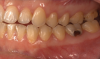

The effects of ENDS on caries activity has not been well established. A few studies suggest that vaping may increase the cariogenic potential, pointing to increased acid production from propylene glycol heating, sweet flavors, sucrose, viscous aerosol, higher bacterial attachment to tooth surface, increased biofilm formation, decreased enamel hardness, and dry mouth (Figure 1 and Figure 2).28

Fig 1. and Fig 2. Multiple carious posterior teeth after use of e-cigs. Fig 1: Gross caries on maxillary and mandibular right first molars; Fig 2: Gross buccal caries on a mandibular left first molar. (Reprinted with permission from Journal of Esthetic and Restorative Dentistry.28 Copyright 2020, John Wiley and Sons).